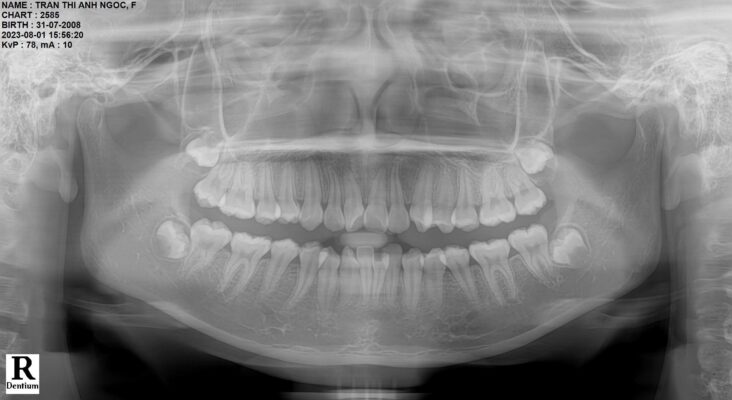

Nếu như trước đây, việc chẩn đoán xương hàm chủ yếu dựa trên phim X-quang 2 chiều (2D) khiến bác sĩ khó quan sát chính xác toàn bộ cấu trúc bên trong miệng, thì ngày nay, công nghệ CT Conebeam 3D đã trở thành một cuộc cách mạng trong nha khoa với chẩn đoán hình ảnh 3 chiều (3D) hiện đại.

Những dữ liệu này sau đó được xử lý bằng phần mềm chuyên dụng để tái dựng thành mô hình 3D sắc nét, phản ánh chính xác cấu trúc xương hàm, răng, chân răng, dây thần kinh và xoang hàm của người bệnh.

Từ đó dễ dàng phát hiện các vấn đề tiềm ẩn như tiêu xương, viêm quanh chân răng cũ, khoảng cách đến dây thần kinh, độ sâu xoang hàm… giúp quá trình lập kế hoạch điều trị trở nên chính xác và cá nhân hóa cho từng khách hàng.